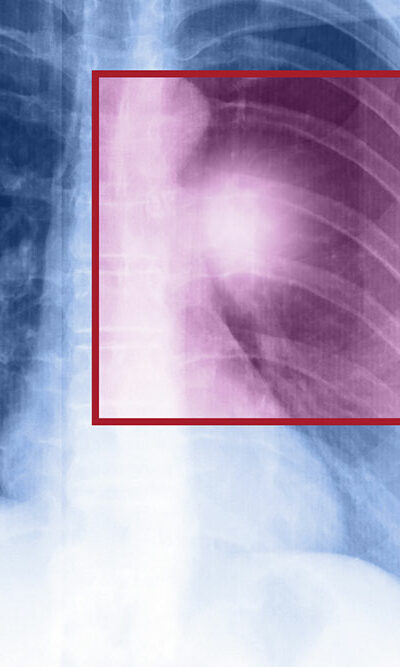

Symptoms and Treatment of Metastatic Lung Cancer

Cancer is a life-threatening condition that typically forms particularly in one area or region of the body and this region is known as the primary site. Cancer cells can travel to other parts of the body, breaking away from its primary site through the bloodstream or the lymph system and is called metastasis. Metastatic lung cancer occurs when cancer cells break away from a tumor formed in the lungs and travel to other parts of the body through the blood or the lymph system. Even though the cancer cells have traveled and spread to a new location in the body, it is still named after the body part from where it all started. It is common for lung cancer to metastasize even before it is diagnosed, as symptoms generally do not show up when the lung cancer is already present. The most common sites of metastasis for lung cancer are the other lung, adrenal gland, bones, brain, and liver. Metastatic lung cancer is very different from recurring lung cancer, as recurring lung cancer affects the same part of the lung after being treated rather than moving to some other parts of the body. A metastatic cancer is always caused by the cancer cells developing in some other regions and traveling to another part of the body. Symptoms of metastatic lung cancer The symptoms of metastatic lung cancer are related to the area to which cancer spreads and these symptoms can be general. These general symptoms are often confused with some other issues. Hence, this condition is very difficult to identify as it does not always cause discernible symptoms. However, we have listed some of the common symptoms which are related to the site where a new tumor has developed: Bones Patients with lung cancer have a 40 percent chance of developing bone metastases which include symptoms such as pain.